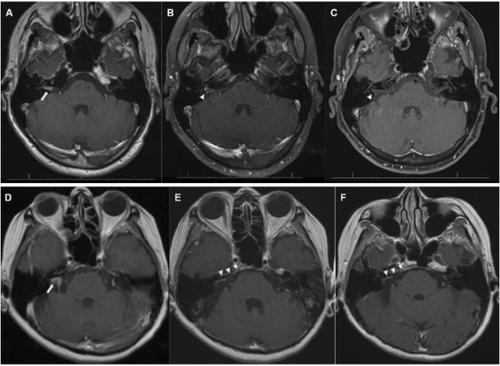

One theoretical disadvantage of the retrosigmoid approach is the inability to visualize tumor at the fundus of the internal auditory canal, potentially leading to a higher risk of residual tumor even when the surgeon reports a gross total resection. We sought to compare MRI enhancement patterns and their persistence following retrosigmoid and translabyrinthine vestibular schwannoma (VS) resection.

Adults aged ≥ 18 years old who underwent translabyrinthine or retrosigmoid approaches for resection of a sporadic vestibular schwannoma (VS) at a single tertiary care institution were eligible for inclusion in this cohort study. Patterns of enhancement on postoperative MRI, when present, were qualitatively described as linear or nodular. Multivariable logistic regression was used to adjust for tumor size and resection extent.

After surgeon-reported gross total resection, linear enhancement was present in 24/141 (17.0%) and nodular enhancement in 2/141 (1.4%) cases. Both patterns showed high rates of spontaneous resolution, with 3/24 (12.5%) of linear enhancements persisting on ≥ 2 scans and no nodular enhancements (0/2) persisting. Among patients with less than gross total resection, when present, nodular enhancement was more likely to persist (3/5, 60.0%) than linear enhancement (3/8, 38.0%, p < 0.001). Approach was not associated with odds of nodular enhancement (OR for retrosigmoid vs. translabyrinthine 0.36, 95% Cl 0.05–1.89, p = 0.2). Similarly, surgical approach was not significantly associated with linear enhancement (p = 0.41). Surgeon-reported gross total resection was associated with reduced odds of nodular enhancement for translabyrinthine (OR 0.07, 95% CI 0.00–0.63, p = 0.04) but not retrosigmoid (OR 0.09, 95% CI 0.00–2.76, p = 0.13).

Postoperative enhancement typically resolves after gross total resection, but when present, surgeon-reported resection extent is a key predictor of persistence. However, our findings suggest that in retrosigmoid cases—where limited visualization of the fundus may increase the risk of residual tumor—surgeon reports of gross total resection may be less reliable.